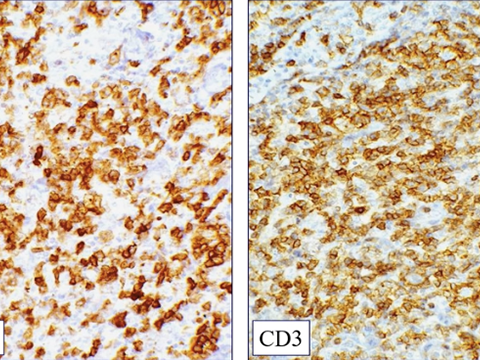

Angioimmunoblastic T-cell lymphoma and other nodal lymphomas of T follicular helper (TFH) cell origin

- Angioimmunoblastic T-cell lymphoma